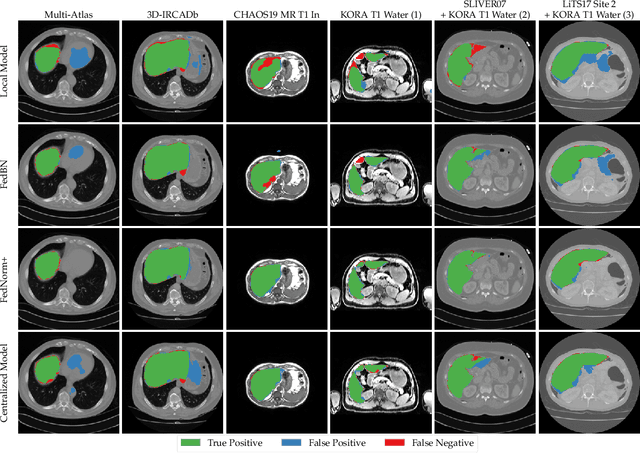

Given the high incidence and effective treatment options for liver diseases, they are of great socioeconomic importance. One of the most common methods for analyzing CT and MRI images for diagnosis and follow-up treatment is liver segmentation. Recent advances in deep learning have demonstrated encouraging results for automatic liver segmentation. Despite this, their success depends primarily on the availability of an annotated database, which is often not available because of privacy concerns. Federated Learning has been recently proposed as a solution to alleviate these challenges by training a shared global model on distributed clients without access to their local databases. Nevertheless, Federated Learning does not perform well when it is trained on a high degree of heterogeneity of image data due to multi-modal imaging, such as CT and MRI, and multiple scanner types. To this end, we propose Fednorm and its extension \fednormp, two Federated Learning algorithms that use a modality-based normalization technique. Specifically, Fednorm normalizes the features on a client-level, while Fednorm+ employs the modality information of single slices in the feature normalization. Our methods were validated using 428 patients from six publicly available databases and compared to state-of-the-art Federated Learning algorithms and baseline models in heterogeneous settings (multi-institutional, multi-modal data). The experimental results demonstrate that our methods show an overall acceptable performance, achieve Dice per patient scores up to 0.961, consistently outperform locally trained models, and are on par or slightly better than centralized models.